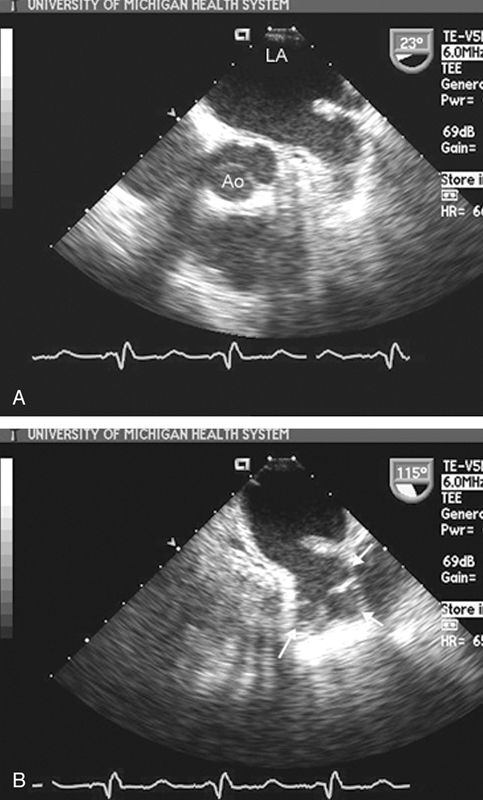

فحوصات تشخيصية لبعض امراض القلب والشرايين التاجية